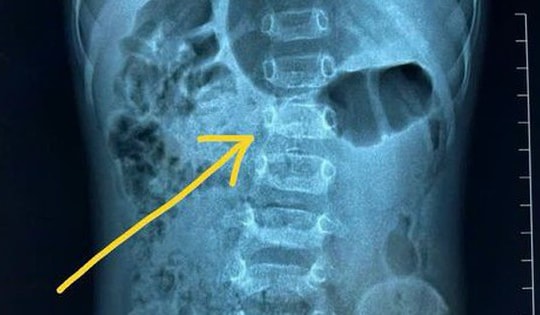

Thanh niên 19 tuổi bất ngờ phát hiện cột sống cong 50 độ, thừa nhận thường xuyên làm việc này trong lúc tập gym

Nam sinh bị cong cột sống ở tuổi 19 cho biết đã tập gym hơn 2 năm nay. Trong khoảng thời gian này, anh liên tục nâng tạ nặng tới 200kg.